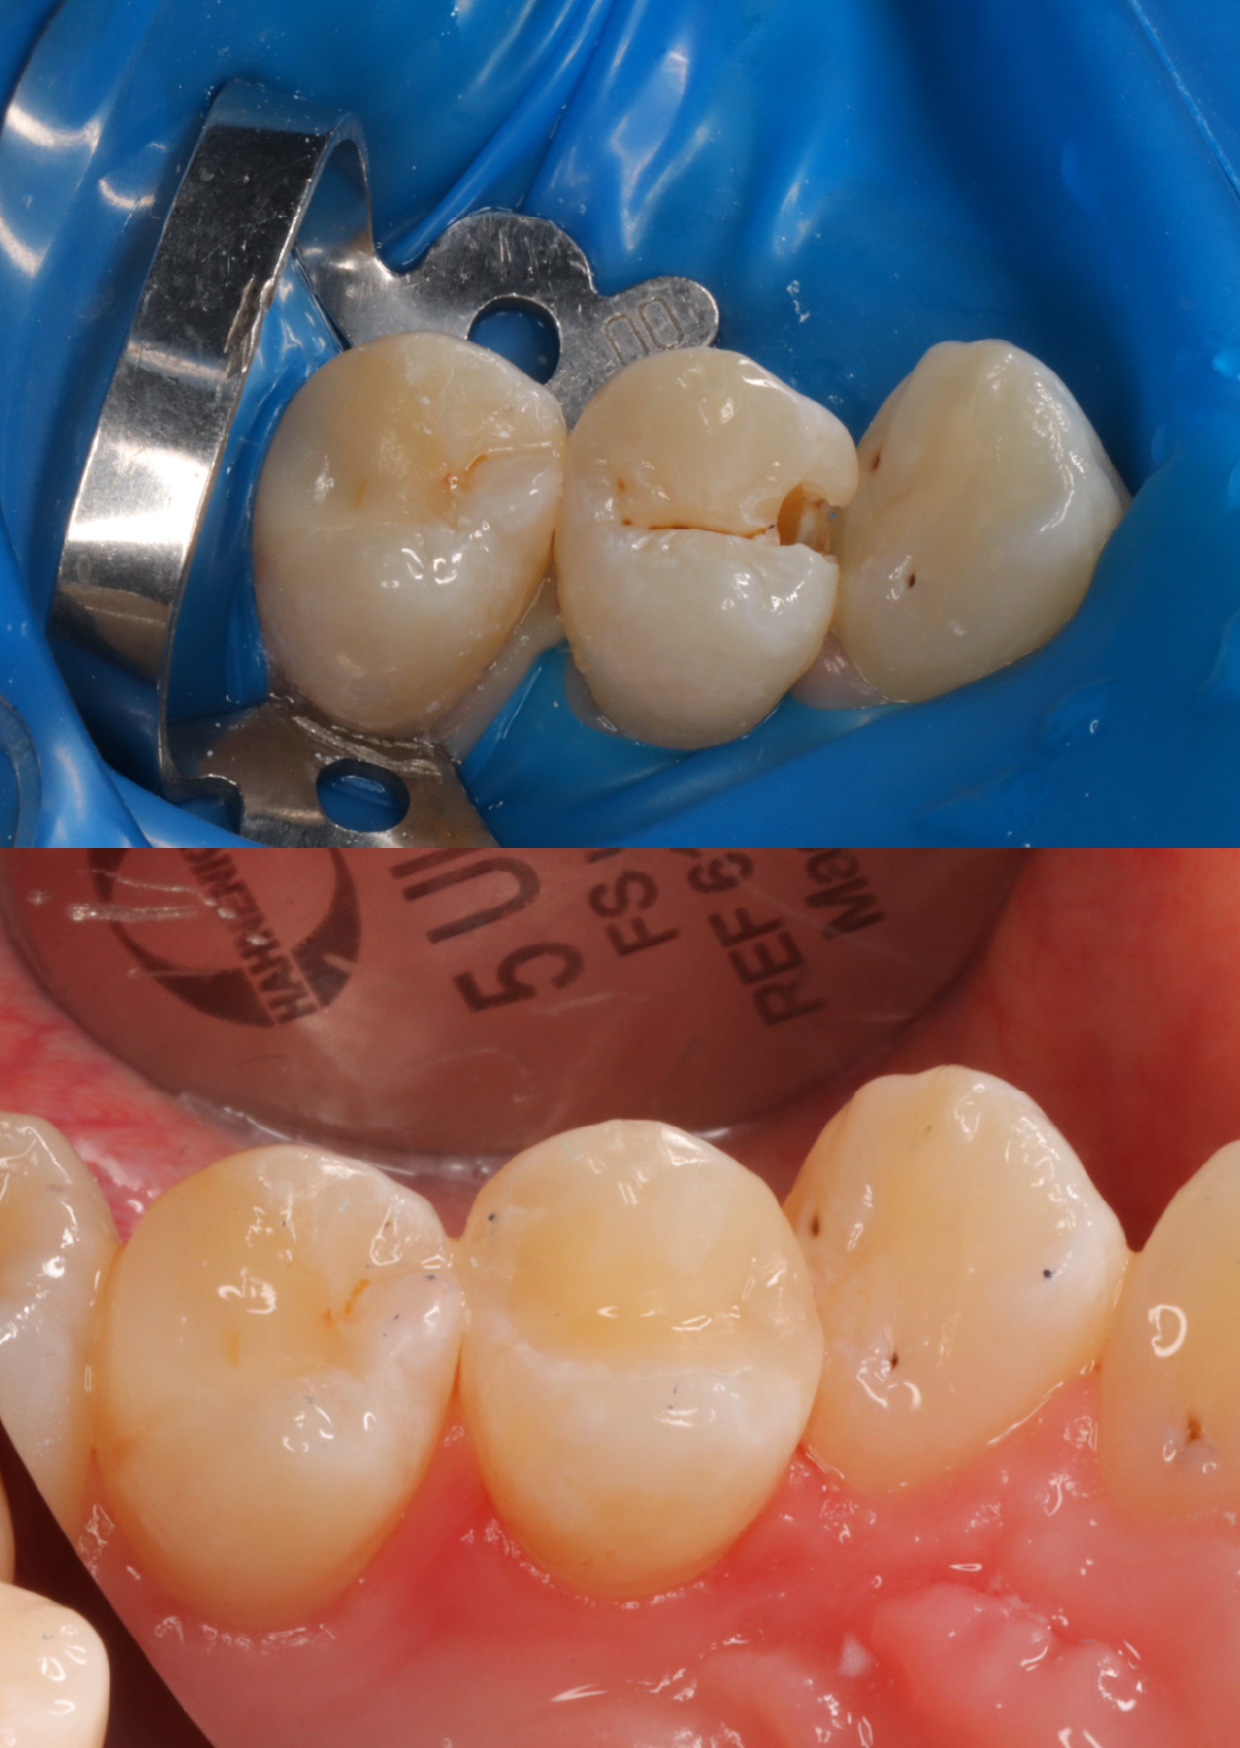

Случай достаточно классический, но осложнен расположением соседнего зуба, клыка. он развернулся на 45 градусов, поэтому мешает и пациенту, качественно прочистить зуб, и врачу в лечении.

Лечение кариеса - это грамотно обезболить, изолировать зуб, аккуратно убрать кариес, не задев соседний зуб, далее поставить специальные матрицы, для того, чтобы воссоздать контактный пункт и потом также бережно заполировать эту стенку.

В итоге: кариес убран, стенка зуба заполирована, пациент обучен домашней межзубной гигиене.